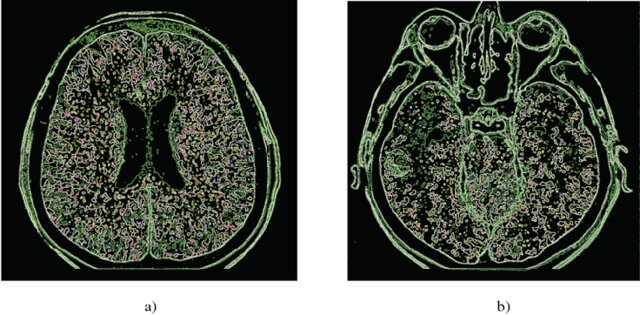

BRAINS retraces the captivating history of neuroimaging—the visualisation of the brain’s structure, function, and biochemical activity—by illustrating the evolution of techniques used to represent the brain over the centuries.

Beginning with foundational methods like X-rays and the pioneering use of electroencephalography (EEG), neuroimaging has progressed to sophisticated technologies such as Magnetic Resonance Imaging (MRI) and Positron Emission Tomography (PET). Each technological leap has enhanced our understanding of the brain’s intricate architecture (structure) and its dynamic processes (function), providing deeper insights into the workings of the nervous system.